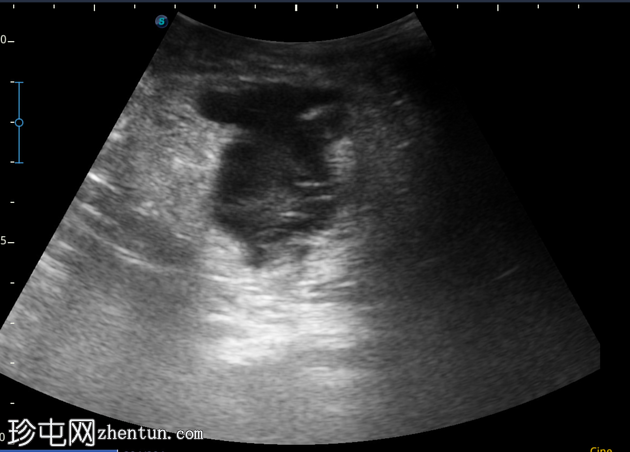

4-10点钟平面

浅表探头

在右前外侧肛周区域(具体位置为10-11点钟方向,紧邻肛壁)观察到一个边界清晰、大小约为5 x 5厘米的低回声病变。病变壁不规则,后部回声增强。病变内部回声提示可能存在肛周脓肿。

在此阶段,未见内部瘘管或与肛管的交通。此外,未检测到明显的病灶周围血管或气体灶。为了更好地评估病变的定位和范围,除了浅表探头外,可能还需要深层探头。